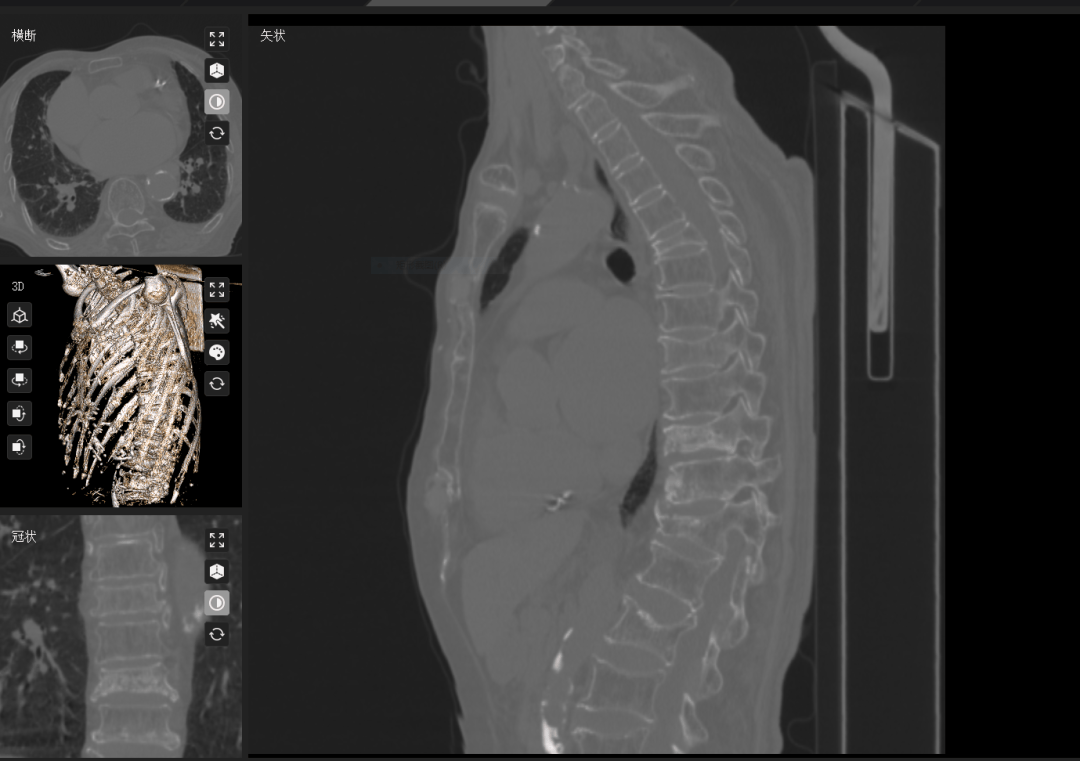

88岁王阿姨:腰疼到直不起身,检查发现腰椎间盘突出。奇怪的是,腿不麻不疼,问题竟藏在“看不见”的地方——脊柱两侧的多裂肌严重萎缩,脂肪化;医生解释:这些肌肉就像脊柱的“张力弹簧”,一旦变薄变弱,腰椎失去保护,椎间盘被“压垮”,疼痛自然找上门。甚至导致多发性椎体骨折,胸10骨折不愈合骨坏死。通过数字化骨科技术对脊柱深层肌群进行三维影像重建与功能评估,精准锁定病灶,这种将解剖结构可视化与功能评估数字化的创新模式,为临床揭示了"看不见的病变"与症状之间的因果关联,也为脊柱退行性疾病的精准诊疗开辟了新维度。